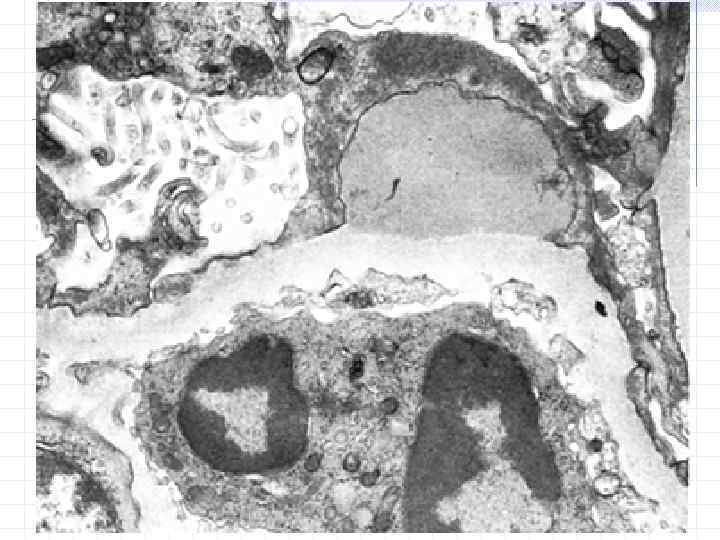

Нейтрофил Диффузный генерализованный эксудативно-пролиферативный гломерулонефрит, субэпителиальные депозиты ( «горбы» )